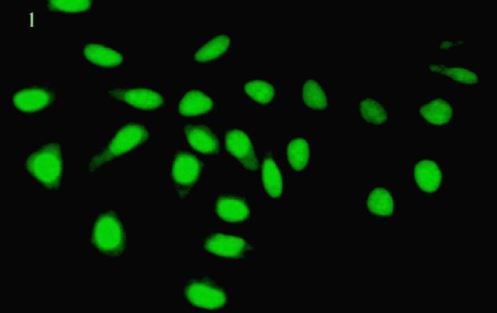

MMP-2 and MMP-9 protein determination in cervical cancer

Prasad, M.P

Biolife; 2014, 2(4), pp 1248-1253

DOI:http://dx.doi.org/10.17812/blj2458

Received: 15 October 2014; Accepted: 30 November 2014; Published: 19 December 2014

Abstract |  Full Paper